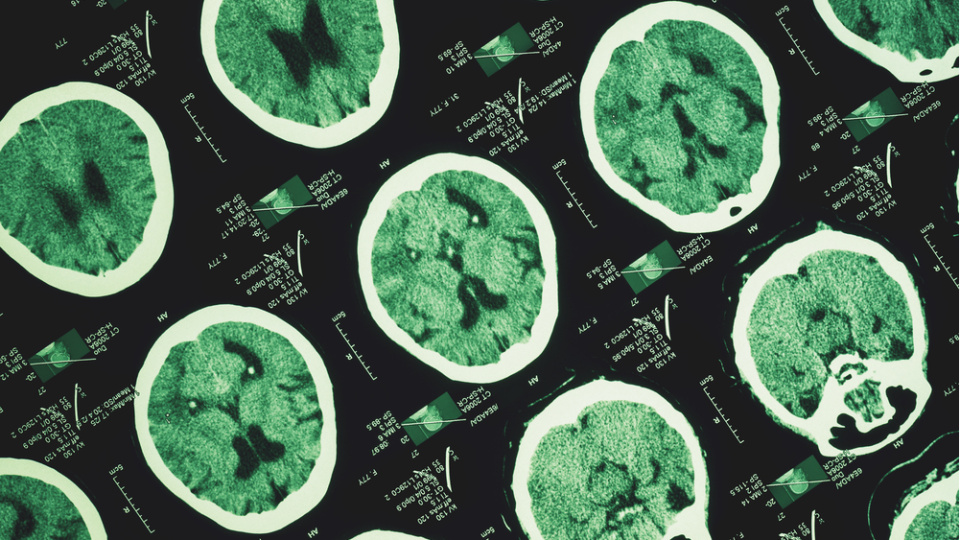

Türk Nöroloji Derneği, 13 Mart Dünya Uyku Günü dolayısıyla yaptığı açıklamada, uykunun nörolojik açıdan beynin en yoğun çalıştığı dönemlerden biri olduğunu belirtti.

Açıklamada, son yıllarda keşfedilen glimfatik sistemin, uyku sırasında beynin adeta temizlik moduna geçtiğini ortaya koyduğu, gün içinde biriken metabolik atıkların ve potansiyel nörotoksik maddelerin bu süreçte temizlendiği ifade edildi.

Bu mekanizmanın bozulmasının, Alzheimer gibi nörodejeneratif hastalıklarla ilişkili olabileceğine dikkat çekilen açıklamada, “Uyku yalnızca enerji toplamak değil, beynin kendini koruması ve yenilemesi için zorunlu bir süreçtir” değerlendirmesi yapıldı.